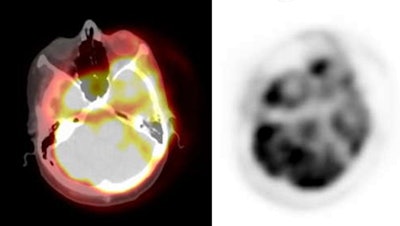

Attenuation correction: The images below are from the same patient. The image on the left is non-attenuation corrected (the lungs and skin surface appear warm). The right image is corrected for attenuation. Note the improved visualization of structures deep within the body. |